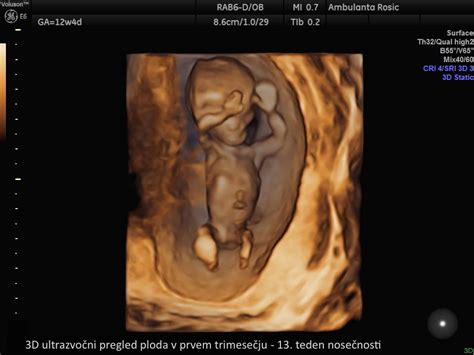

- Pregled nuhalne svetline: Ta ultrazvočni pregled, ki ga stroka priporoča med 11. in 14. tednom nosečnosti, je namenjen določanju tveganja za kromosomske nepravilnosti, kot je Downov sindrom. Izvaja se preko trebuha, natančno se pregledajo posamezni organski sistemi ploda, določi se razvoj kosti, intrakranialnih struktur, srca, prebavnega in urološkega trakta ter se izmeri dolžina ploda od temena do trtice (CRL). Natančno se izmeri razdalja med hrbteničko in kožo na plodovem vratu, kar je osnova za izračun tveganja. Pregled je zakonsko brezplačen za nosečnice, starejše od 35 let, vendar ga priporočajo vsem nosečnicam, saj se dve tretjini otrok z Downovim sindromom rodi ženskam, mlajšim od 35 let.

Kako poteka merjenje nuhalne svetline